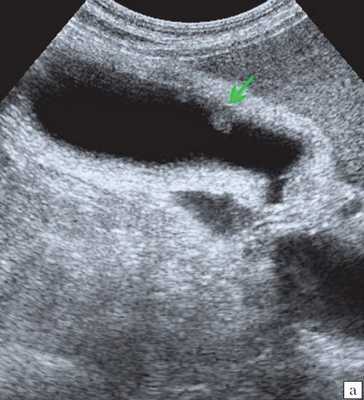

Ультрасонография является эффективным средством выявления полиповидной формы холестероза 8. Традиционной считается следующая сонографическая характеристика холестериновых полипов: неподвижные гиперэхогенные структуры, которые не дают акустической тени и прикрепляются к стенке желчного пузыря. Контуры таких образований, как правило, ровные, а размеры таких образований различны, чаще не превышают 10 мм (рис. 2).

a) Одиночный полип в желчном пузыре (гиперэхогенное пристеночное неподвижное образование, с ровными контурами, без акустической тени).

б) Одиночный полип в желчном пузыре.

в) Полиповидно-сетчатая форма холестероза, полипы размерами до 5 мм, повышенной эхогенности.

г) Одиночный полип в желчном пузыре.